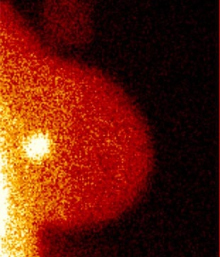

La adición de imágenes moleculares de mama (molecular breast imaging, MBI) a la mamografía convencional permite hallar más cánceres en mujeres con tejido mamario denso y en dosis de radiación aceptables para tamizaje (screening), según un nuevo estudio publicado en la el American Journal of Roentgenology.

Los investigadores incluyeron 1.585 mujeres asintomáticas con mamas densas según resultado de una mamografía previa. Las mujeres se sometieron a una mamografía de tamizaje complementada con MBI a una dosis reducida de 8 mCi de 99mTc-sestamibi con una cámara gamma de teluro de cadmio zinc (una dosis convencional para MBI es de 20-25 mCi). Se calculó la sensibilidad, especificidad, las tasas de retorno y las tasas de detección de cáncer en las mujeres con las dos categorías de tejido mamario denso: "heterogéneo" o "extremadamente" denso.